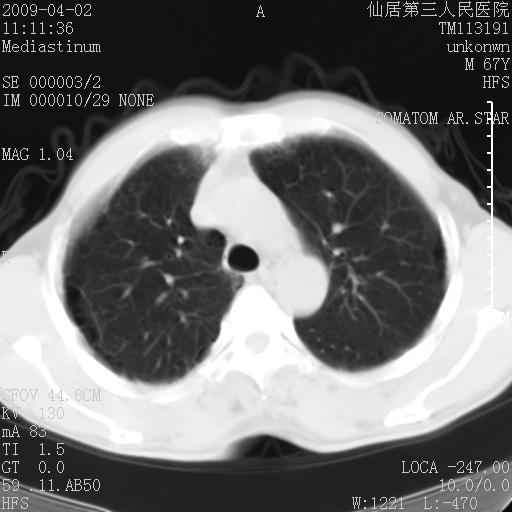

患者老年男性,乏力畏寒来诊,摄胸片示右下肺感染性病变,抗炎两周后复查胸片,无好转有进展。

后做ct平扫表现如下: